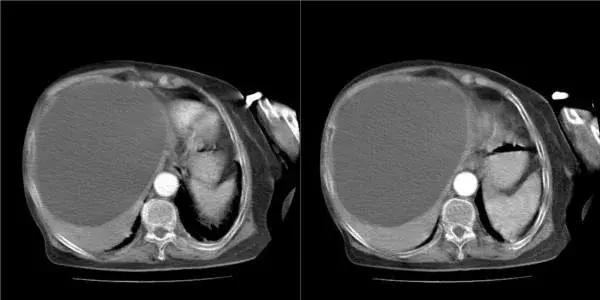

超声检查是肝脏影像学检查首选的方法,具有价廉、便捷、无创等优点。常规超声能显示肝脏大小形态,肝内实质结构、管道系统、血管走向与分布,明确有无肝脏结节、具体的大小与部位、初步鉴别结节的良恶性,适用于常规体检和结节的定期复查。

值得一说的是,随着超声技术的发展,彩色多普勒超声可以诊断直径小于1cm的病变,在有经验的单位,准确率可达90%以上。

对于B超不能明确诊断的,建议做增强CT扫描或MRI检查,对于高度怀疑肝细胞癌的可行“肝动脉造影”检查。

各种影像学检查不但可以配合定性论断,还可以进行定位论断,也就是进一步确定肝脏结节在肝脏上的位置、大小、数目及其与周围组织的关系,为进一步治疗方案提供依据。